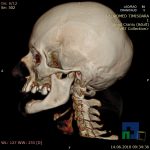

- Diagnosticul fracturilor:

-

- Unice

- Multiple

- Cu înfundare

- Complexe cranio-sinusale

- Complexe cranio-etmoidale

- Complexe cranio-orbitare

- Complexe cranio-faciale